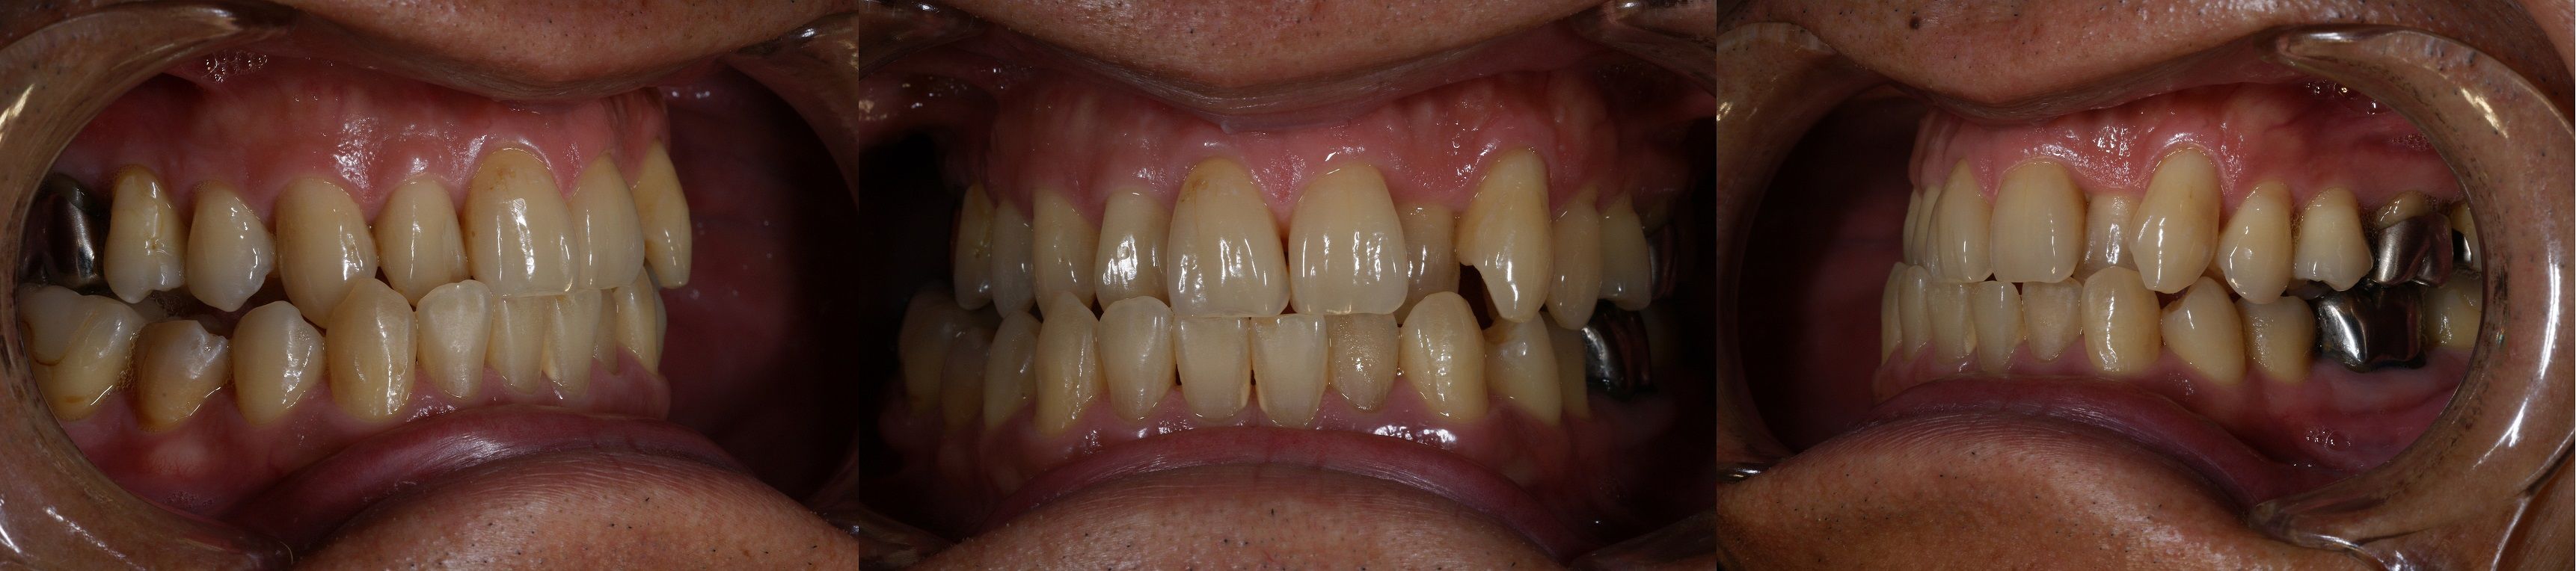

(初診時口腔内写真。これ以上のデータは実際に掲載されたブログでご確認下さい!)

前回のブログの概略を説明しますと、患者さんは初診時53才、男性、会社役員、右上臼歯部の違和感を主訴として来院。通法に従い精密検査終了後問題点を抽出したところ、全体的に歯周病が中~高程度に進行しており、特に咬合において鋏状咬合(Scissors bite)であることが原因となり主訴につながっていると診断。

右上の違和感が、歯周病と咬合の問題によるもので、主にその二点の解決なくして口腔の長期的な健康は得られないと説明したところ、患者さんの理解と同意を得、同時に治療の依頼あり診療を開始。